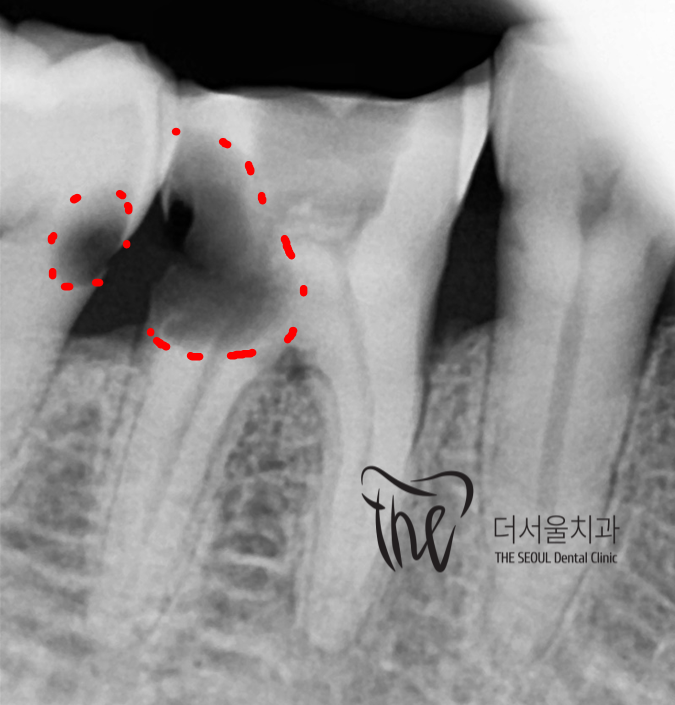

그래서, 사진처럼 해상도 높은 엑스레이를

찍어서 확인을 해야 그 범위를 정확히

파악을 할 수 있습니다.

결국, 사진처럼 치아 사이 충치 진행이

상당히 진행되었다면 발치를 할 수 밖에 없으며

물론, 치아 사이 충치 범위 자체가

그렇게 많이 진행이 되지 않은 거라면

신경치료를 통해서 보존을 할 수 있을텐데,

오늘 보여드린 증례에서는 치관의 1/4 가량이

썩어있었으며 이미 치수괴사에 이르렀기에

보존을 해드린다 한들, 가까운 미래에 다시

치과에 찾아오셔서 임플란트를 할 수 밖에

없는 상황이였습니다.